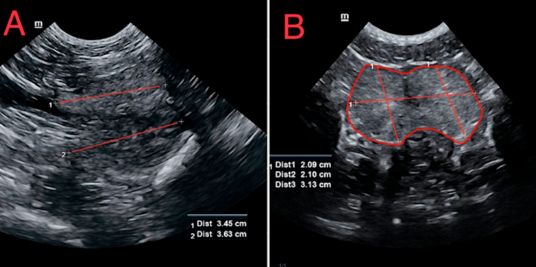

반려견의 전립선 비대 초음파 기준

| 전립선 길이 대 대동맥 내강 직경 비율이 : 3.68 전립선 너비 대 대동맥 내강 직경 비율이 : 4.46 전립선 평균 높이 대 대동맥 내강 직경 비율이 : 3.06 |